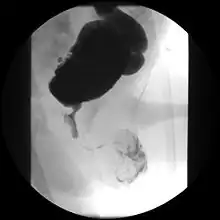

Voiding cystourethrogram (VCUG) is more specific for the diagnosis. Normal plicae circularis are variable in appearance and often not seen on normal VCUGs. PUV on voiding cystourethrogram is characterized by an abrupt tapering of urethral caliber near the verumontanum, with the specific level depending on the developmental variant. Vesicoureteral reflux is also seen in over 50% of cases. Very often the posterior urethra maybe dilated thus making the abrupt narrowing more obvious. the bladder wall may show trabeculations or sacculations or even diverticuli.